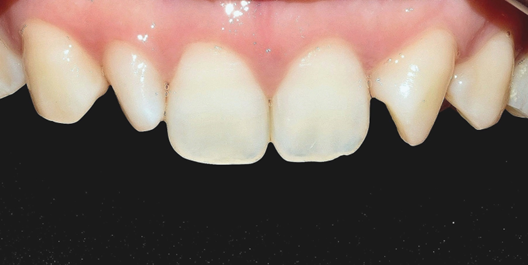

(전) 2021-12-03, (후) 2021-12-08

6개 치아 라미네이트 진행

2022-01-27

왜소치인 치아 1개만 라미네이트 진행

2022-02-08

왜소치와 앞니 파절

4개 치아 라미네이트 진행

라미네이트는 치아의 겉면을 일부 삭제하고, 세라믹으로 제작된 판을 부착하는 보철치료입니다.

왜소치의 상당 부분은 무삭제 혹은 최소삭제 라미네이트 시술도 고려해 볼 수 있기 때문에

영구치를 보존하면서도 자연스럽고 심미적으로 우수한 결과를 기대할 수 있습니다.